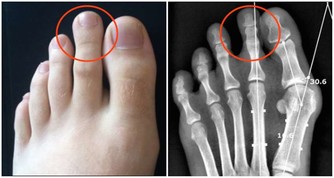

其三、踮足功。就是腳尖著地,腳後跟擡起,能擡多高擡多高。胃的經絡通過腳的第二趾和第三趾之間,胃經的原穴也在腳趾的關節部位。胃腸功能較弱的人,不妨經常鍛煉腳趾。你可以踮著腳尖走路你也可以試試踮著腳尖站個十來分鐘,記住在踮腳尖時要盡可能地把腳踮得高一點,這樣效果才會好!